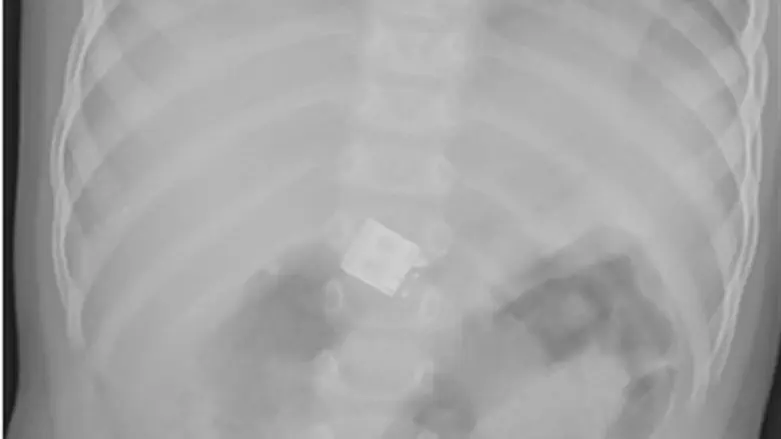

לדברי ההורים, הם ראו את הפעוט בולע גוף זר, ולאחר מכן הוא החל להקיא. רופאי 'טרם' באשקלון החישו את הפעוט לצילום רנטגן בו נצפה MINI USB בבטנו.

בבירור שנעשה התברר כי הפעוט בלע צ'יפ MINI USB אשר מקשר עכבר wireless למחשב.